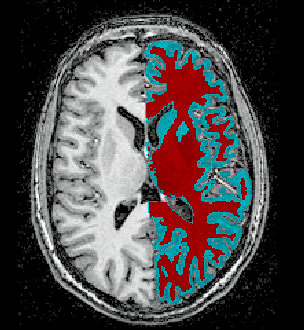

Sujet1212substblanchegrise.PNG